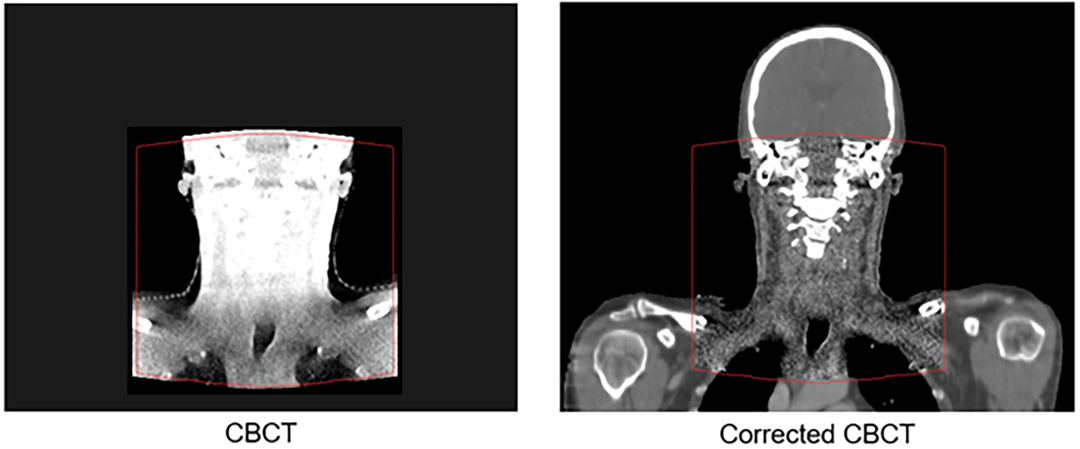

The Corrected CBCT algorithm works in an iterative manner with two main stages; conversion, and correction. These stages are alternated until convergence. The initial stage finds a conversion from the CBCT intensity scale to the planning CT HU intensity scale, and the second finds a correction map that (for each CBCT voxel) removes low frequency artifacts.

This method works for all CBCTs, with no calibration needed and no possibility of changes to the CBCT geometry. In case of limited FOV, parts outside the FOV are copied from the deformed planning CT to the CBCT